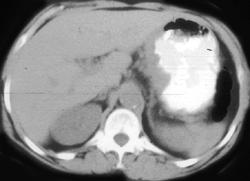

GIST Tumor